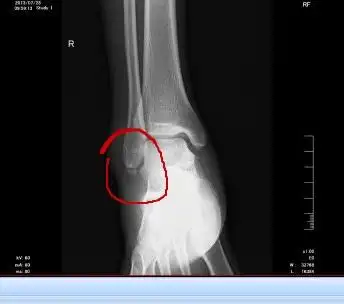

小孩踝关节x光片正常